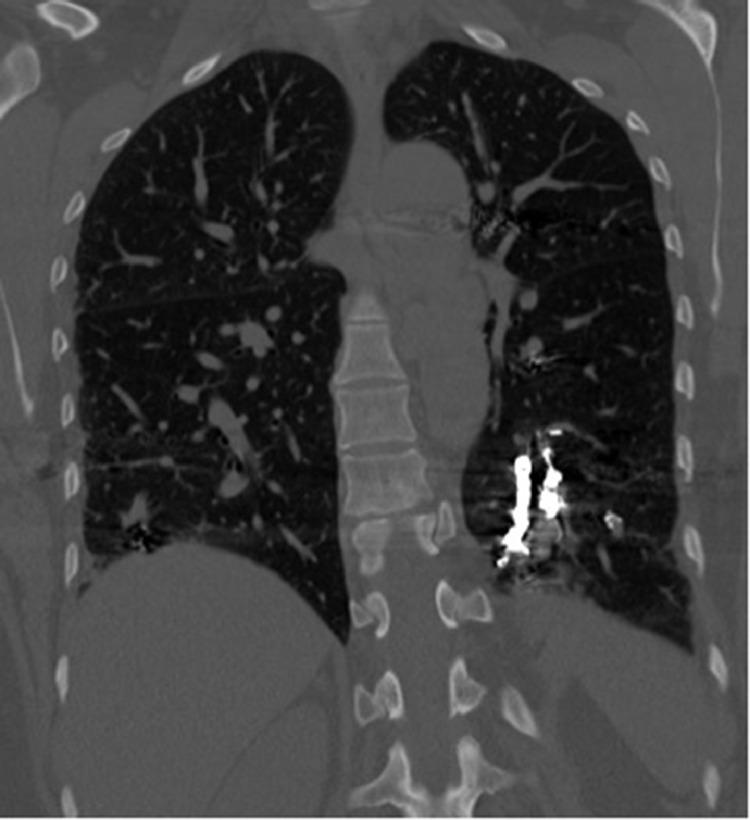

Pulmonary arteriovenous malformations develop in approximately 50% of hereditary hemorrhagic telangiectasia patients. Pulmonary arteriovenous malformations are often treated with coil embolization therapy. We report a case of a 45-year-old female with multiple pulmonary arteriovenous malformations due to underlying hereditary hemorrhagic telangiectasia who had undergone 14 coil embolization procedures over 16 years. She presented with sudden onset severe, unremitting, nonproductive cough from a foreign body sensation in the airway. Computed tomography of the chest demonstrated a metallic foreign body extending from the left lower lobe of the lung into the left mainstem bronchus and trachea. Bronchoscopy-guided removal of the foreign body revealed an intact embolization coil placed 8 years prior to presentation had partially migrated through the vessel and airway walls into the airway lumen, extending from the left lower lobe bronchus to the left mainstem bronchus. Coil migration is a rare, but potentially dangerous, complication of coil embolization therapy.

约50%的遗传性出血性毛细血管扩张症患者会出现肺动静脉畸形。肺动静脉畸形通常采用弹簧圈栓塞疗法进行治疗。我们报告一例45岁女性患者,因潜在的遗传性出血性毛细血管扩张症患有多发性肺动静脉畸形,在16年期间接受了14次弹簧圈栓塞手术。她因气道内有异物感而突然出现严重、持续、无痰咳嗽。胸部计算机断层扫描显示一个金属异物从左肺下叶延伸至左主支气管和气管。支气管镜引导下取出异物发现,一个在就诊前8年放置的完整栓塞弹簧圈已部分穿过血管壁和气道壁进入气道腔,从左肺下叶支气管延伸至左主支气管。弹簧圈移位是弹簧圈栓塞治疗一种罕见但可能危险的并发症。